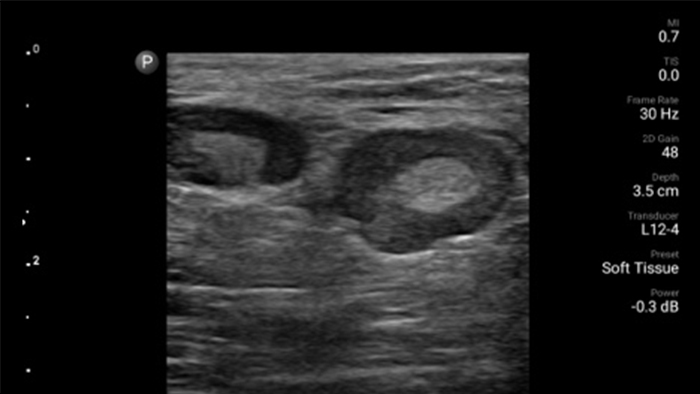

Get the full picture with clear whole-body imagery for a fast, accurate response during an emergency.

• 4 to 1 MHz extended operating frequency range • 2D, color Doppler, M-mode, advanced XRES and multivariate harmonic imaging • High-resolution imaging for abdominal and cardiac applications: Cardiac, OB/GYN, Lung, Abdomen and FAST imaging preset optimizations Lumify aids life-saving technology in prehospital setting